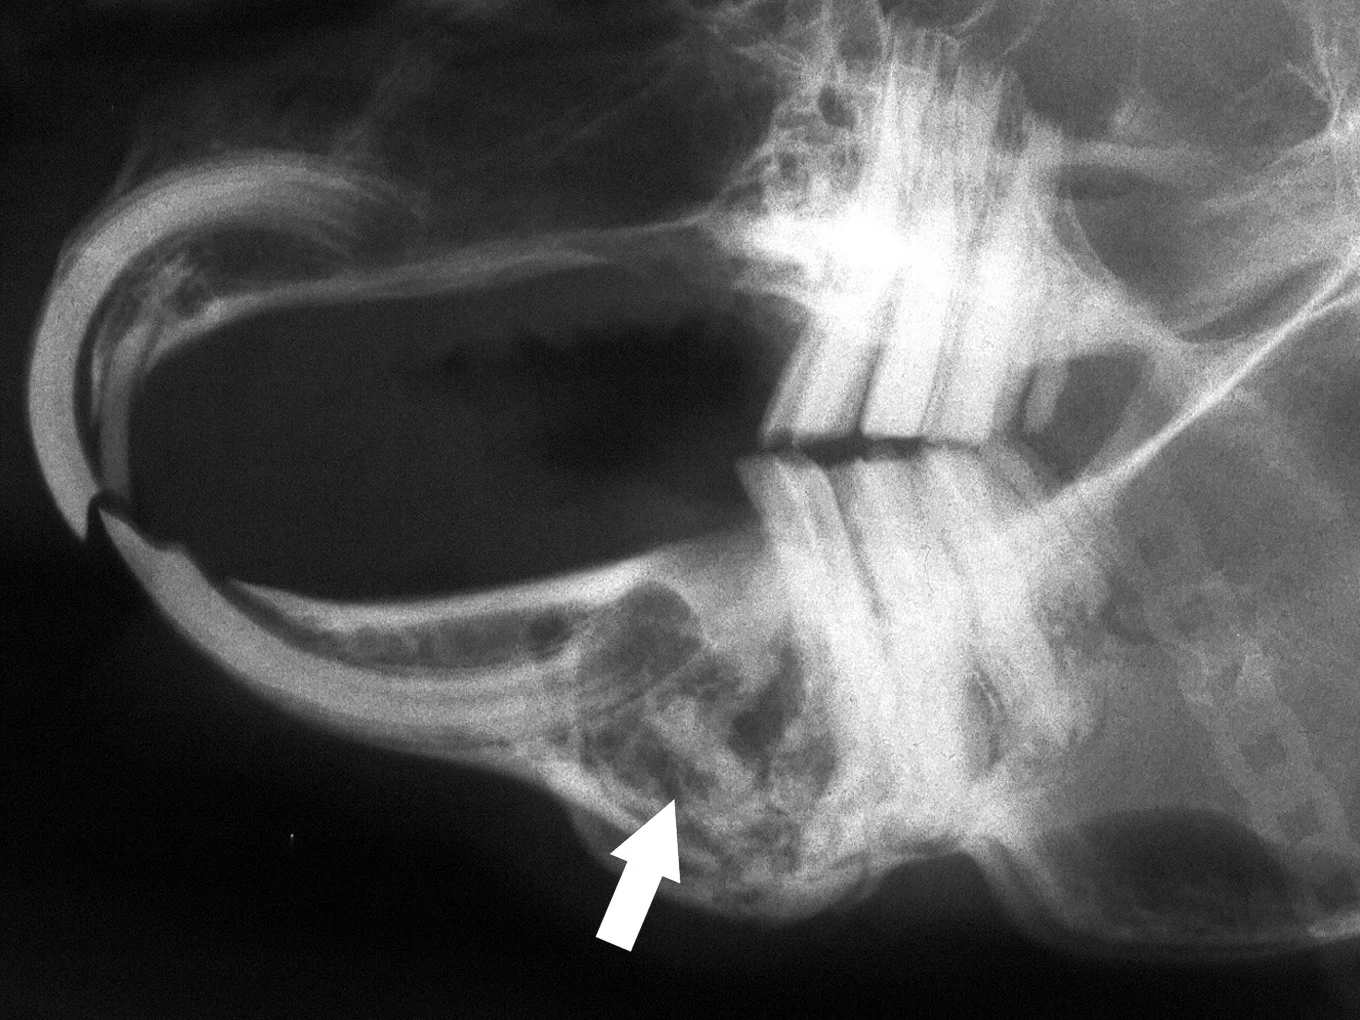

Formation of dental-related abscesses is common in pet rabbits. Most facial abscesses are a sequela to acquired dental disease, particularly dental disease as a result of metabolic bone disease or tooth fracture. Frequently, they develop from periapical infection of mandibular cheek teeth and typically involve both hard and soft tissues. Therefore, common radiographic abnormalities include a fragment of a mandibular cheek tooth associated with mandibular osteomyelitis. The cheek tooth fragment is usually visible in a circular radiolucent lesion that contains purulent material (Figure A).